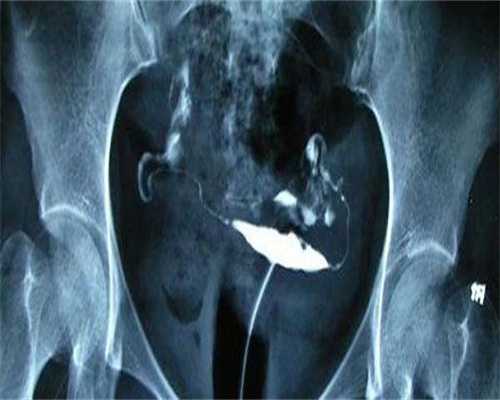

冻卵适合一些需要恶性肿瘤、卵巢早衰、事业心强、年龄大于40岁等情况的女性,这样可以保存她们的生育能力,或者是延长生育能力;而胚胎冷冻适合试管周期中暂不能移植的女性,或者是第一次试管移植会后,还有多余健康优质胚胎的,可以将胚胎进行冷冻,可以等有生育需求的时候在进行解冻移植,不用再次促排。

冻卵是先促排卵,获得多个优质卵子,然后在把它们进行冷冻,等到后面有生育需求的时候在解冻,与男性的结合形成胚胎移植到子宫怀孕;而胚胎冷冻也是想促排卵获得优质卵子,与男性精子体外受精形成胚胎,但是不适合鲜胚移植,从而就需要冷冻胚胎,等满足条件或在进行移植,也就是我们常说的冻胚移植。